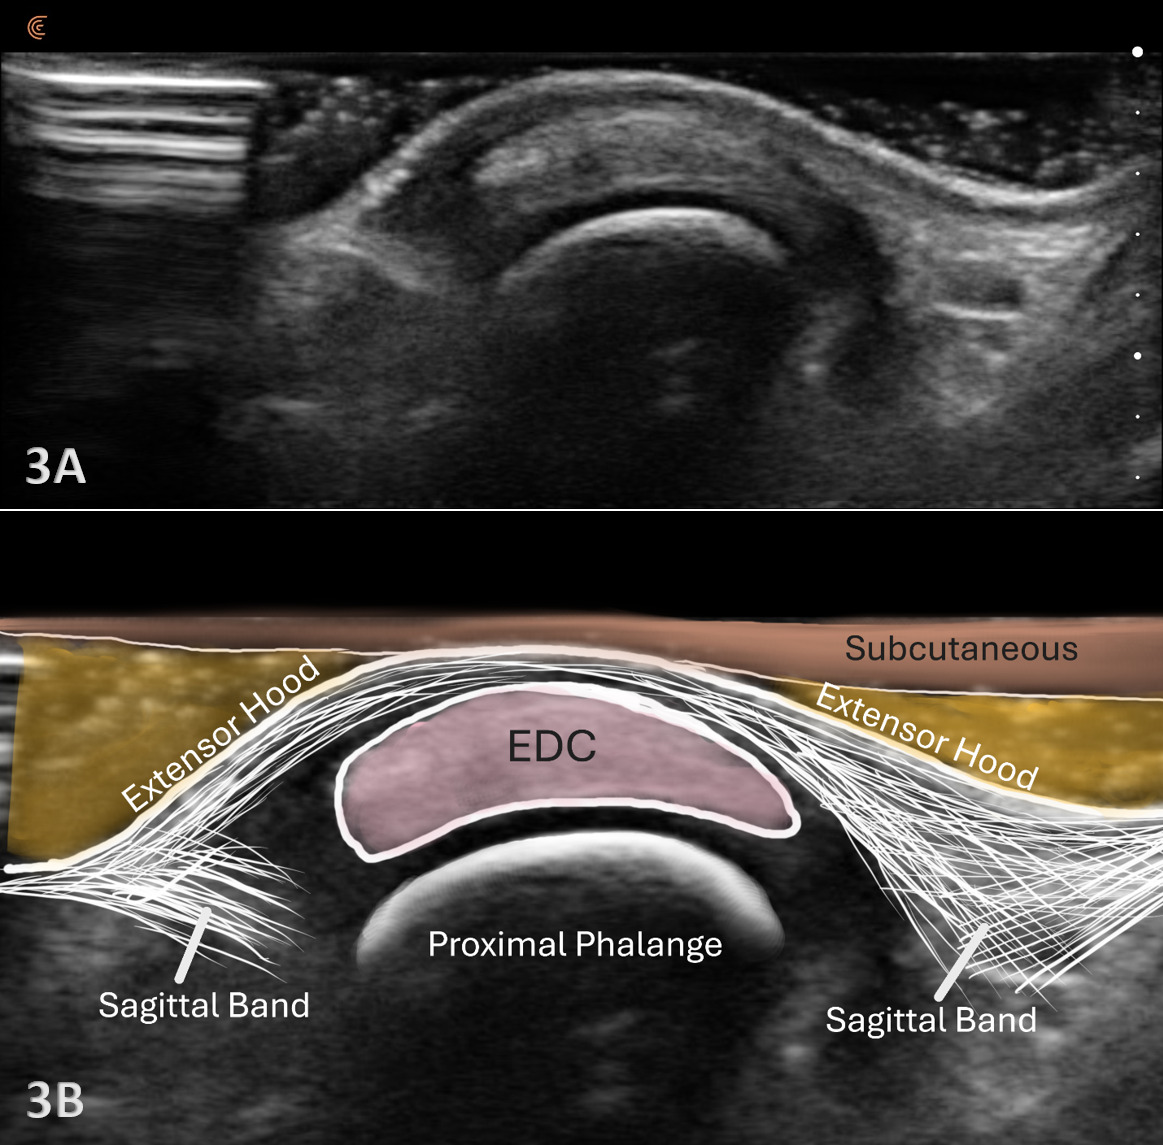

Examination Protocol Normal Sonographic Appearance

The extensor tendon can be examined in both long axis (LAX) and short axis (SAX) views. The tendons can each be seen at the MCP and PIP joints. The hyperechoic outline of the metacarpal and proximal phalanx will be seen at the MCP joint, while the proximal phalanx and middle phalanx will be visualized at the PIP joint. The extensor tendon will be an echogenic fibrillar structure in appearance. In the LAX view, the tendons will become smaller as they run more distally, making them slightly more difficult to visualize. In the SAX view, the tendon should be oval and fibular and should sit in the central position over the metacarpal. The soundhead may need to be toggled at the distal tendons’ insertion to avoid anisotropy. Dynamic visualization can be performed with resisted or active movement of the wrist or fingers.

At the level of the metacarpophalangeal (MCP) joint, the extensor digitorum tendon is joined by the sagittal bands, which are part of the extensor hood. The sagittal bands on the extensor surface are further attached volarly to the palmar plate of the MCP joint. The sagittal bands are critical for stabilizing the tendon, limiting proximal excursion of the tendon, and assisting with extension at the PIP joint.